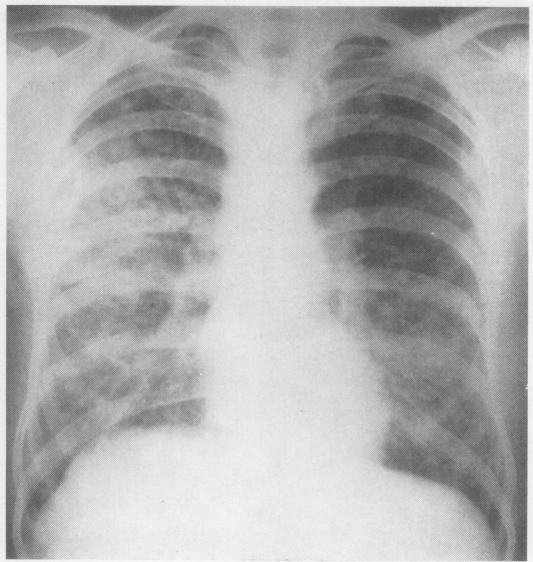

In assessing patients suffering from farmer's lung, the acute stage must be distinguished from the chronic stage of the disease. The conspicuous radiographic signs in the acute farmer's lung episode and the often dramatic clearing make an important contribution to the diagnosis. The radiographic changes in chronic farmer's lung are not specific and cover a wide range of appearances. Even minor nodular changes are significant. Farmer's lung, acute and chronic, is not a disease predominantly characterized by a defect in gas exchange. During the acute illness the reduction in diffusing capacity is often accompanied by a decrease in lung volumes; the pulmonary function profile of the chronic stage is variable. In only a relatively small proportion of chronic farmer's lung patients does a defect in gas exchange predominate, and in some it may be manifest only during exercise. Airway obstruction is a feature of chronic farmer's lung. In chronic farmer's lung patients discrepancies between the severity of complaints and results of pulmonary function tests are not infrequent. In some patients with considerable disability conventional pulmonary function studies may demonstrate little or no impairment of the functions measured. In patients suffering from an acute farmer's lung episode, serological tests should be positive, possibly in high titre. In the chronic stage of the disease the chance of finding positive serology in a patient diminishes with the length of time elapsed since the last acute episode. The period of serological transition appears to be the third year.